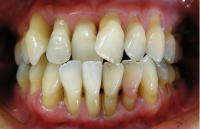

ビフォー・アフター写真・・・症例1

ビフォー2枚

(口元にコンプレックスがありました。右上の前歯は内側に引っ込んでいます。)

(写真1)

初診時の写真(患者さんのスナップ写真より)。

口元にコンプレックスがあり、

笑う時もてのひらで口元を隠していました。

(写真2)

正面観・・・右上の前歯が内側に入り込んでいます。

下の前歯も歯茎が下がりグラグラと動揺しています。